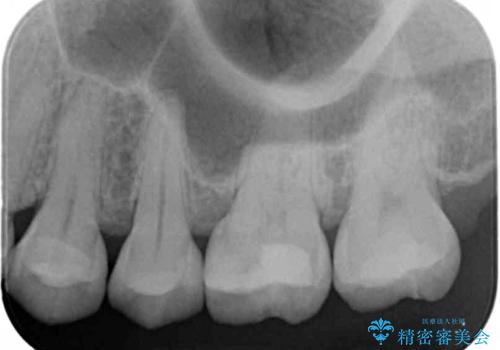

- 検査の結果、歯と歯の間に虫歯が見つかった患者様です。

白く目立たないものでの治療をご希望されたため、セラミックインレーでの治療となりました。

- 左上5 セラミックインレー 77,000円費用は治療当時の料金となります

歯と歯の間は虫歯の好発部位です。

適合の良いセラミックインレーで修復することで見た目の綺麗さを保ったまま治療することができます。